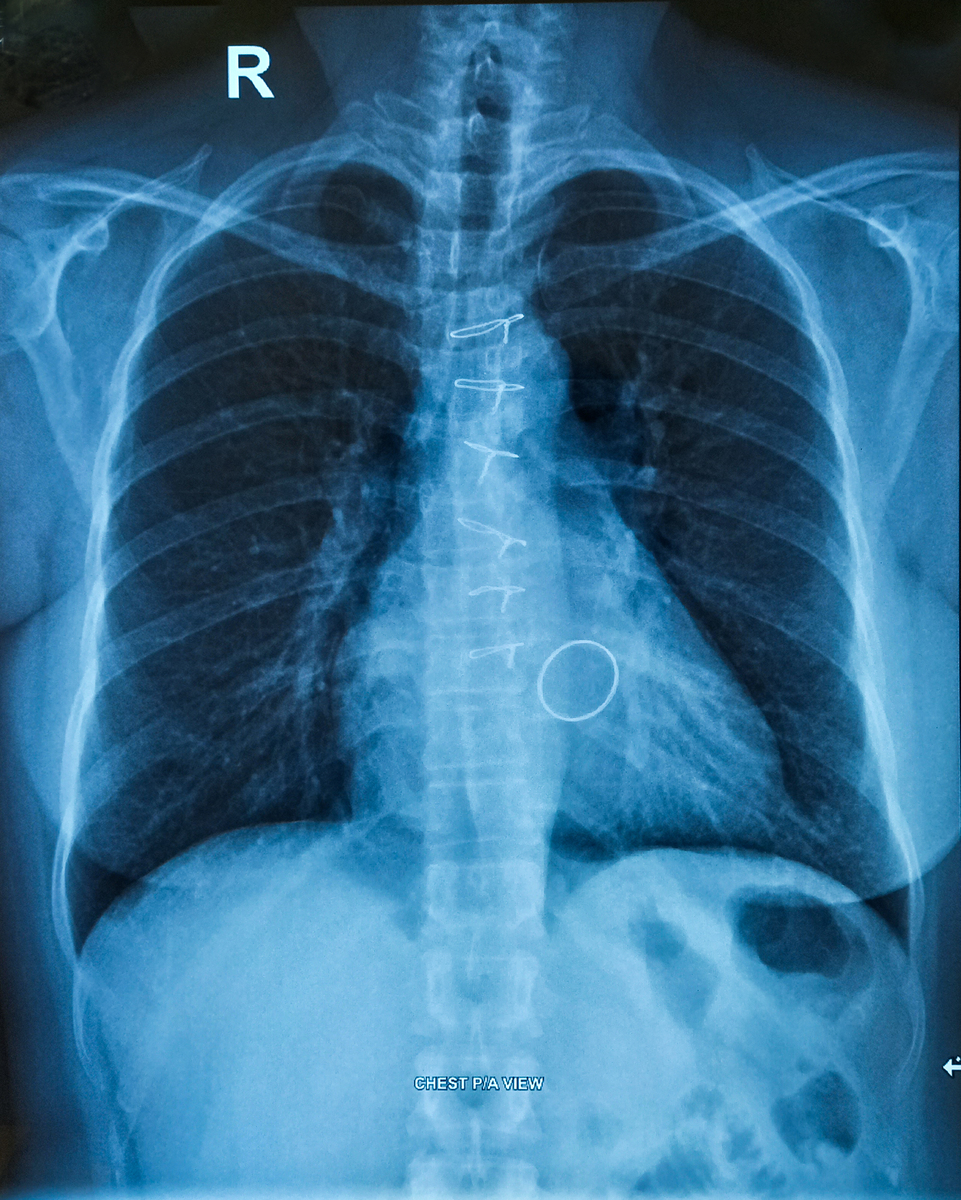

胸片检查是一种常见的影像学检查方法,用于评估胸部内部结构,可以帮助医生发现和诊断多种疾病和病变。以下是一些常见的疾病和病变,胸片检查可以帮助发现:

需要注意的是,胸片检查可以发现上述疾病和病变的征象,但不能确定具体的诊断,通常需要进一步的检查和评估来确诊。